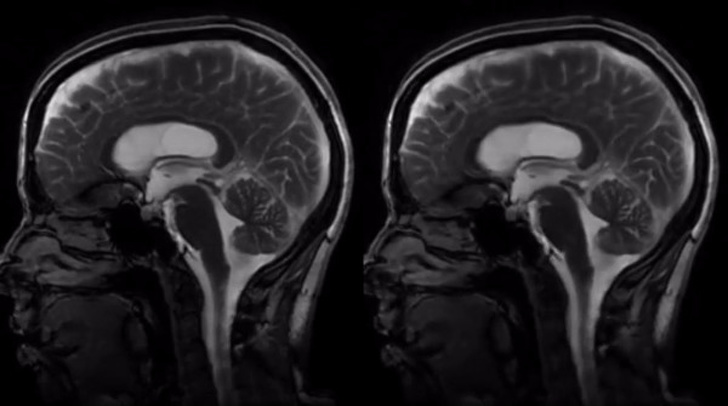

Посилена МРТ (праворуч) вперше фіксує рух мозку всередині черепа